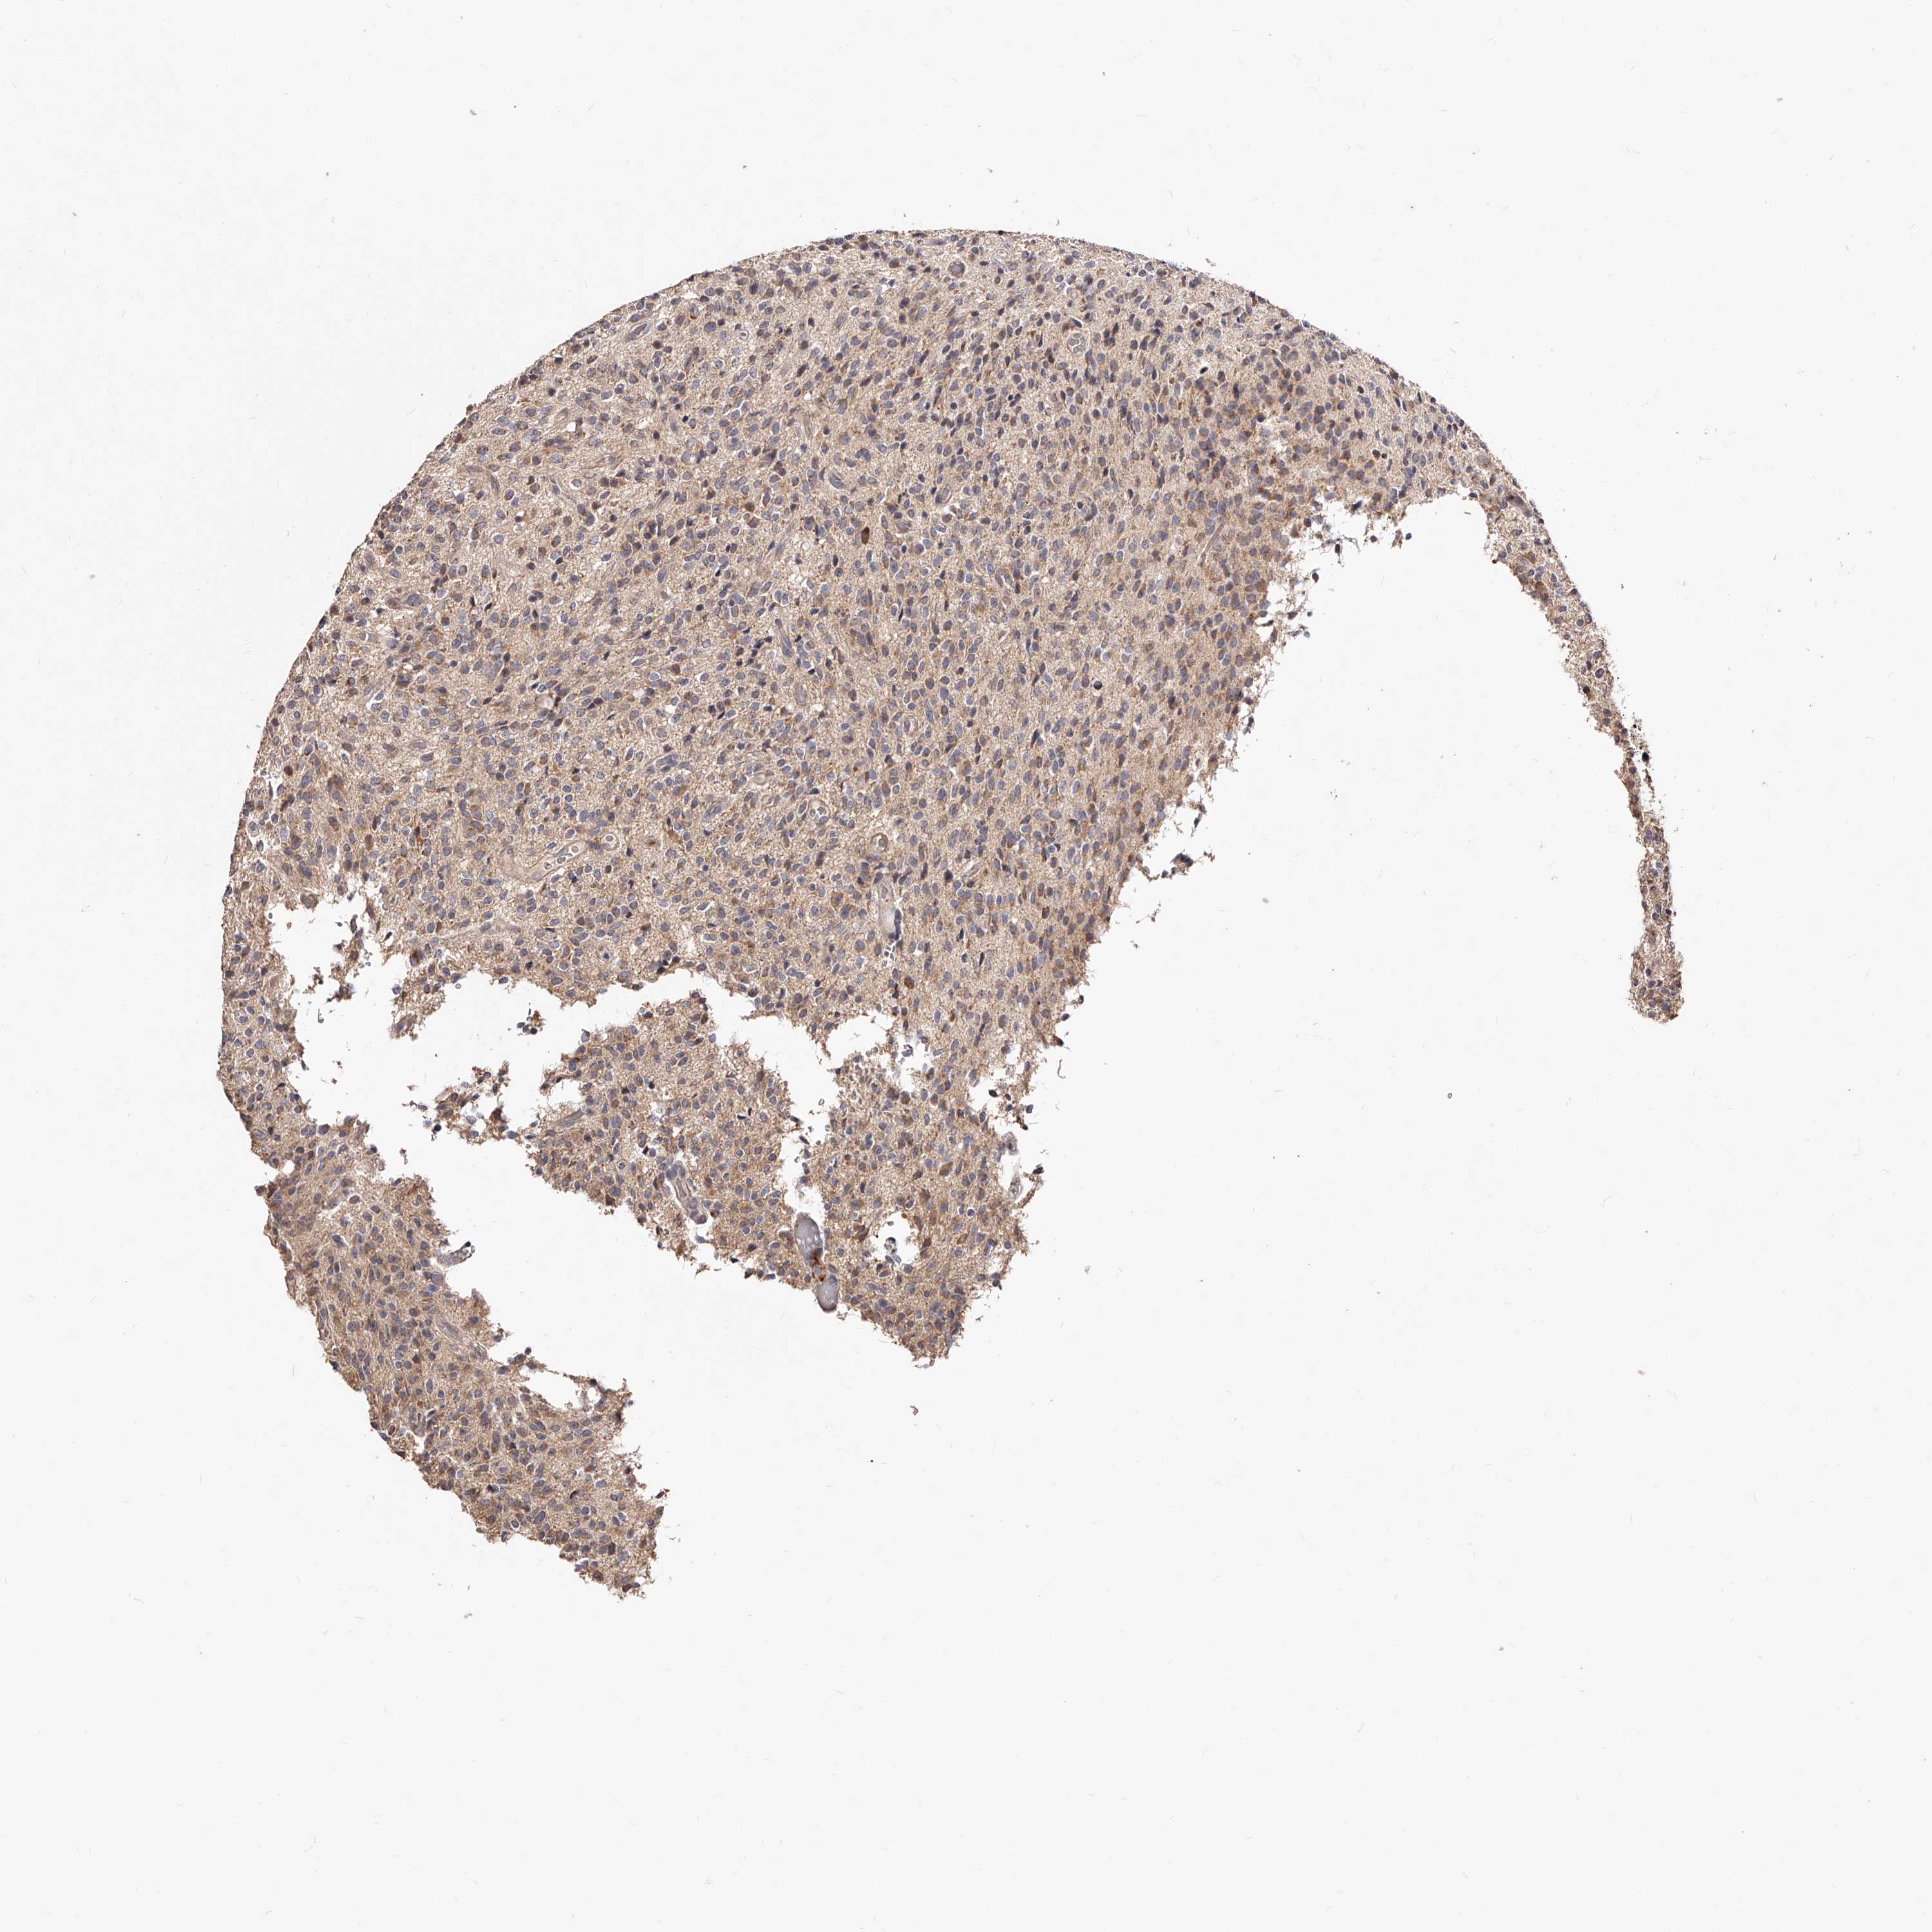

GLIOMA - Protein expressioni

A mouse-over function shows sample information and annotation data. Click on an image to view it in a full screen mode. Samples can be filtered based on level of antibody staining by selecting one or several of the following categories: high, medium, low and not detected. The assay and annotation is described here.

Note that samples used for immunohistochemistry by the Human Protein Atlas do not correspond to samples in the TCGA dataset.

Antibody stainingi

Antibody staining in the annotated cell types in the current human tissue is reported as not detected, low, medium, or high, based on conventional immunohistochemistry profiling in selected tissues. This score is based on the combination of the staining intensity and fraction of stained cells.

Each image is clickable and will lead to virtual microscopy that enables deeper exploration of all samples and also displays staining intensity scores, fraction scores and subcellular localization as well as patient and tissue information for each sample.

Antibody HPA024761

Antibody HPA029557

Staining

High

Medium

Low

Not detected

Intensity

Strong

Moderate

Weak

Negative

Quantity

>75%

75%-25%

<25%

None

Location

Nuclear

Cytoplasmic/membranous

Cytoplasmic/membranous,nuclear

Glioma, malignant, High grade

Glioma, malignant, Low grade

Glioblastoma, NOS